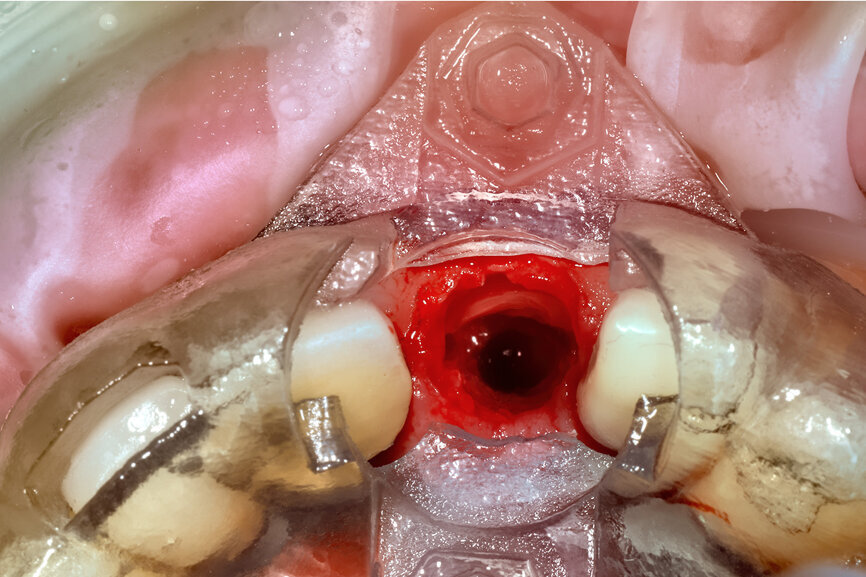

Fig. 23: The implant, seen prior to placement,

using the R2GATE surgical carrier for full-template guidance through the sleeveless guide.

Fig. 24a: Depth control and rotational positioning were accurately

confirmed with the notch indicator on the template corresponding with the insertion tool (a). The occlusal view illustrated that the anti-rotational internal

conical–hexagonal connection was positioned towards the facial aspect (b).

Prior to the guided drilling, a Gates–Glidden drill was used to remove any gutta-percha within the root. Utilising the tooth-borne template and the first insert, initial long shaper drills (IS1, IS2) were used to reach the apex of the root (Root Membrane Kit; Fig. 17). A periapical radiograph confirmed that the apex length had been reached and that all the gutta-percha had been removed (Fig. 18). The second insert had a metal cylinder that allowed for the long, round diamond drills to shape the root into the desired crescent shape (Fig. 19a). The insert was removed to access the palatal root (Fig. 19b). Using appropriate instrumentation such as periotomes, elvatomes or FRINGS forceps (both TBS Dental), the palatal root was carefully removed (Fig. 20). A periapical radiograph confirmed that the palatal root had been completely removed (Fig. 21). The next insert contained the final diameter to receive the guided sleeveless drills for osteotomy preparation (Fig. 22a). The osteotomy was prepared to avoid proximity to the remaining root fragment while leaving sufficient restorative space, as previously planned in the software simulation (Fig. 22b). Implant placement (AnyRidge, MegaGen) was facilitated by the R2GATE surgical carrier for full-template guidance at the appropriate torque values (Fig. 23). Depth control and rotational positioning were accurately confirmed with the notch indicated on the template to correspond with the insertion tool (Fig. 24).